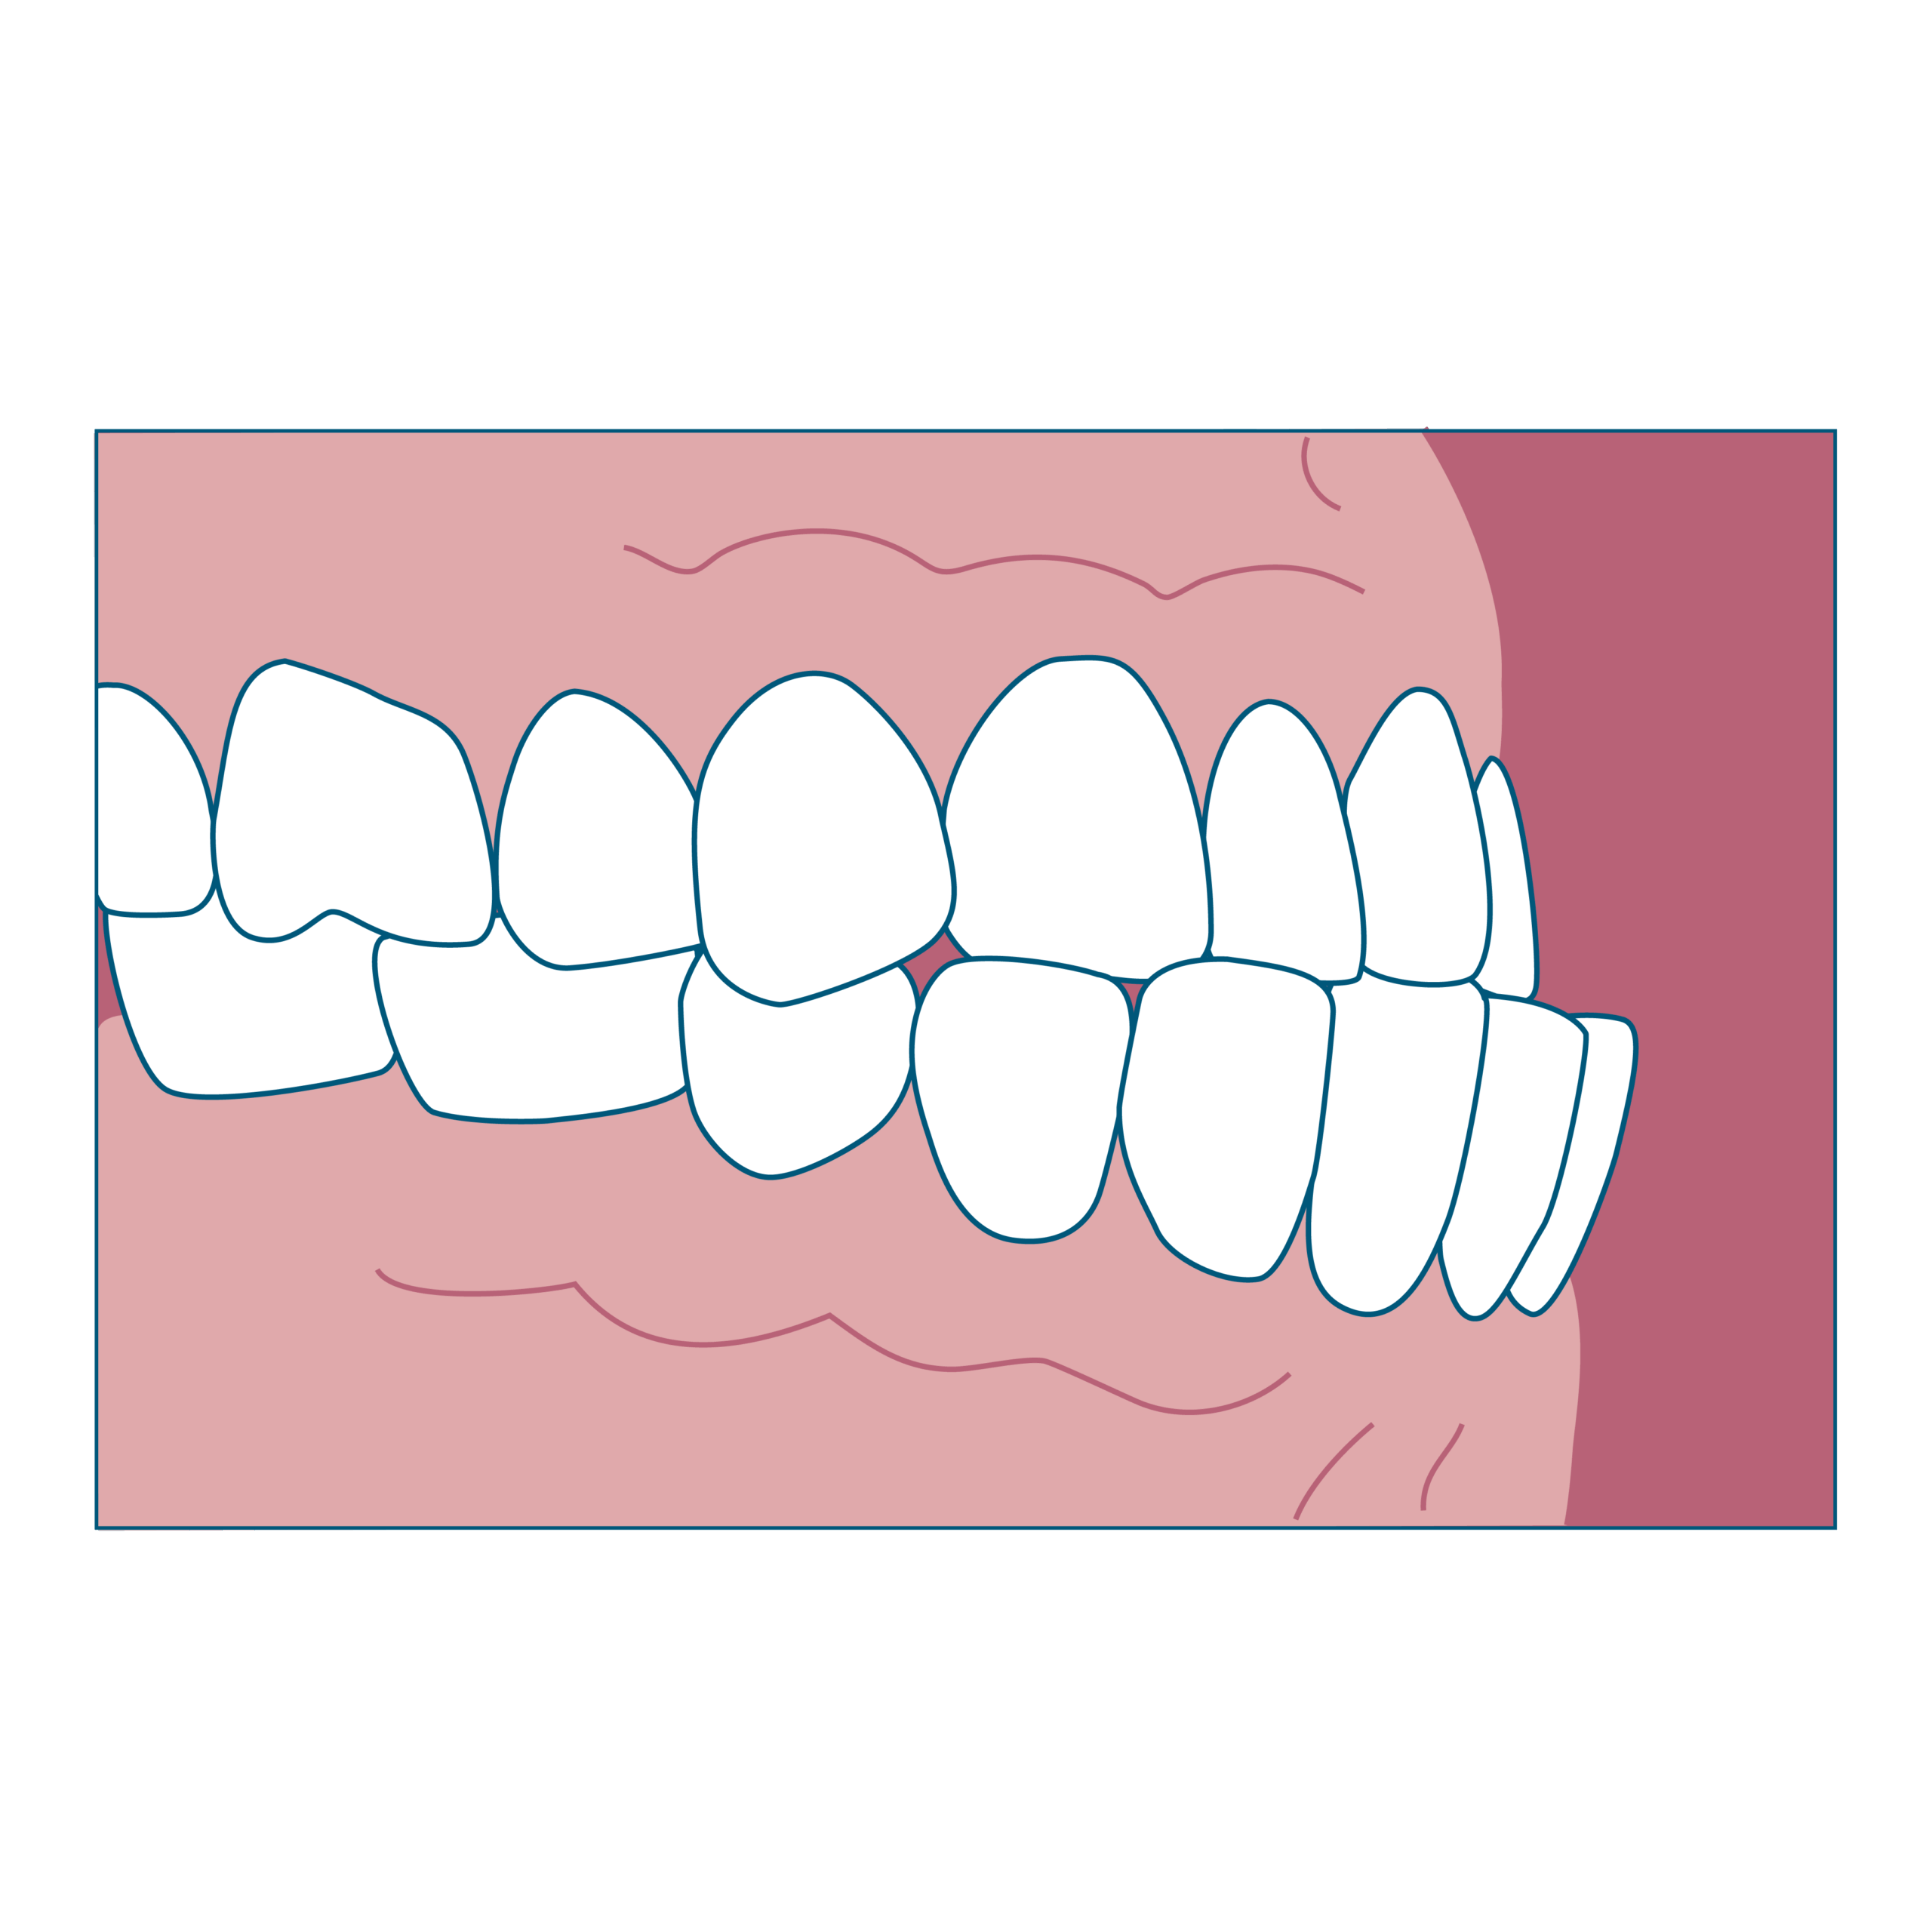

② 受け口(下の前歯が上の前歯より前に出ている)

特徴

- 下あごが前に出ているように見える

- 発音しづらい音があることも

始め時

治療開始時期の目安は、6~8歳前後の早めの時期が望ましいといえます。受け口の場合、骨格的な問題があることが多く上あごの成長が足りず下あごが前に出てしまっている状態のため、思春期でのさらなる下あごの成長に備えて、上顎前方牽引装置(じょうがくぜんぽうけんいんそうち)などの装置を使用して上あごを成長させておく必要があります。

ワンポイント

はやめに相談して「経過観察だけでOK」なのか、「今から装置を使った方がいいのか」を見極めることが大切です。